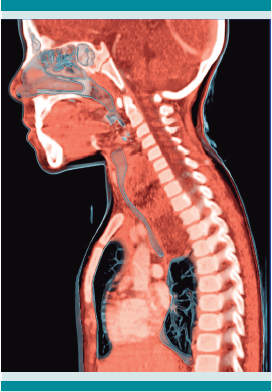

Las radiografías postero-anterior y lateral de tórax evidenciaron ensanchamiento mediastinal, de predominio superior hacia la derecha y desplazamiento con compresión anterior de la luz de la tráquea, secundario al ensanchamiento del espacio retro-traqueal, respectivamente. (Figura 1) La tomografía computada de cuello y mediastino simple, con contraste, reportó una lesión neoformativa del espacio prevertebral (mediastinal posterior y superior) que comprimía y desplazaba anteriormente la tráquea y el esófago, con calcificaciones lineales escasas y estructuras vasculares del cuello desplazadas lateralmente. Figuras 2 y 3

Después de ingresar al INP, la radiografía de tórax y la tomografía lograron delimitar la ubicación de la neoplasia en el segmento posterior del mediastino, de acuerdo con la taxonomía de Carter y sus colaboradores.3Figura 4